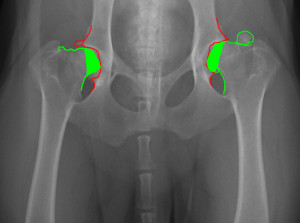

זה צילום של אגן אשר רואים שינויים בקצוות של עצם הירך אשר נגרמים ע''י שחיקה של הסחוס ונגיעה של עצם כנגד עצם אשר גורם לשינויים בעצמות.